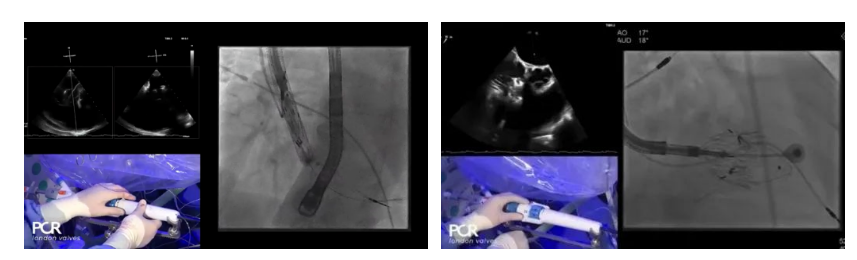

二、LuX-Valve Plus經(jīng)血管三尖瓣置換歐洲經(jīng)驗(yàn):德國(guó)Mainz中心Ralph Stephan von Bardeleben教授“首秀”

在Thomas Modine教授的線上指導(dǎo)下,德國(guó)Mainz中心Ralph Stephan von Bardeleben教授完成了LuX-Valve Plus經(jīng)血管三尖瓣置換系統(tǒng)在其所在中心的首例植入,術(shù)后Stephan教授高度贊揚(yáng)LuX-Valve Plus人工三尖瓣瓣膜“植入過程高度可控,安全有效”。接受治療的是一例82歲的高齡男性患者,術(shù)前NYHAⅢ級(jí),因復(fù)發(fā)心衰入院,有逾5年的慢性房顫病史。這例患者因特殊的解剖結(jié)構(gòu)以及較大的三尖瓣瓣環(huán),有起搏器植入史,被所有其他經(jīng)導(dǎo)管三尖瓣修復(fù)或置換器械的臨床排除在外,因此等了一年半才等到此次LuX-Valve Plus的手術(shù)機(jī)會(huì),實(shí)屬不易。

手術(shù)在全麻狀態(tài)下開展,采用經(jīng)右側(cè)頸靜脈入路的方式將輸送器送入患者心臟內(nèi),在TEE及DSA引導(dǎo)下調(diào)整輸送器頭端角度,使得輸送器與三尖瓣瓣環(huán)平面垂直。在輸送器進(jìn)入右心室后釋放室間隔錨定裝置,而后釋放瓣葉夾持件(2個(gè)耳片結(jié)構(gòu))成垂直狀態(tài)。在TEE及DSA確定夾持件固定至三尖瓣葉根部且位于右室側(cè)后釋放人工瓣心房側(cè)盤片。隨后調(diào)整瓣膜同軸性以及室間隔錨定件位置(貼合室間隔),前推藏針管并固定,進(jìn)而釋放室間隔錨定裝置,并再次確認(rèn)瓣膜位置、穩(wěn)定性及同軸性,合攏輸送鞘后撤出輸送器,完成LuX-Valve Plus人工三尖瓣瓣膜的植入。